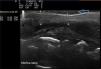

The possibility of performing a diagnostic biopsy was discussed with the family, but, given the cosmetic repercussion, it was decided to use skin ultrasound to confirm the clinical diagnostic suspicion. The ultrasound device employed was the Mylab™25 (Esaote) with a compact linear 18MHz probe. The study was used to support the clinical diagnosis and in particular to ensure correct monitoring of the disease. To perform an accurate study of dermal and epidermal thickness requires a thick layer of gel to obtain a high-quality image; pressure must not be applied to the skin, as this could distort the image. The ultrasound image revealed thinning of the epidermal layer and of the dermosubdermal space, with increased echogenicity of the dermis compared with the adjacent skin (Fig. 2). Doppler mode did not reveal increased vascularization in the area of the lesion. The neurological examination was rigorously normal, and additional laboratory tests were not requested. A diagnosis of inactive linear morphea was made on the basis of the clinical appearance and a compatible ultrasound image, and it was decided to take a wait-and-see approach.

The difference in thickness between affected skin and normal skin does not correlate with disease activity. The different characteristics that should be taken into consideration are overall echogenicity of the lesion, hypoechogenicity of the hypodermis, and increased vascularization of the deep dermis. These parameters, which do appear to correlate with increased clinical activity,8 were evaluated in our patient and enabled us to take a wait-and-see approach. When morphea is in a clinically stable phase, skin ultrasound reveals only a minimal difference in overall echogenicity between affected skin and normal skin, as was found in our patient.9,10